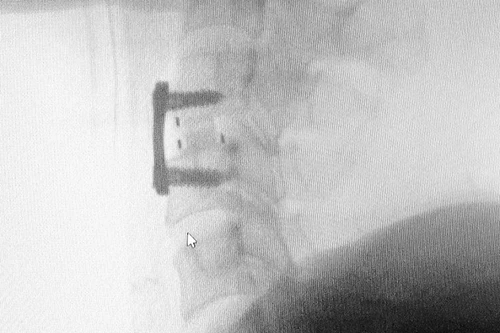

Mổ kết hợp ghép xương và chỉnh trục xương cho bệnh nhân đã phẫu thuật 6 tháng trước